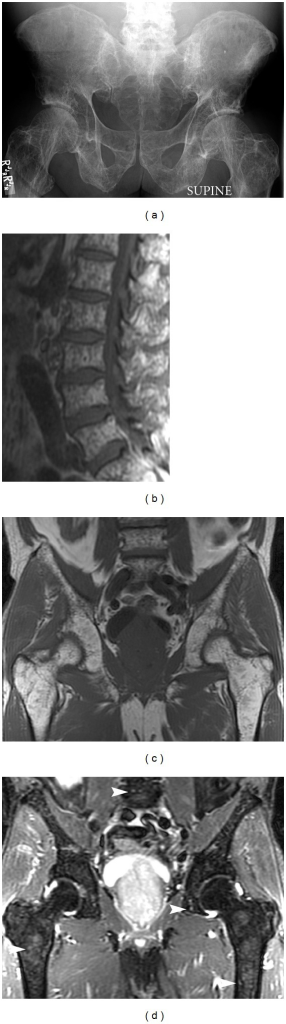

Lateral skull radiograph demonstrating classic multiple punched-out lytic lesions ('raindrop skull') characteristic of multiple myeloma. The lesions have well-defined margins without sclerotic rim. No periosteal reaction. Similar lesions are present throughout the axial skeleton. SPEP shows M-spike and bone marrow biopsy confirms >10% clonal plasma cells.